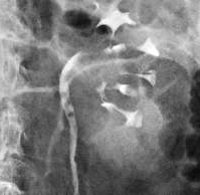

При цистоскопии обнаруживают опухолевидное образование, выступающее из устья мочеточника. В некоторых случаях видны выделения крови. Рентгенологические исследования с контрастированием позволяют определить локализацию рака мочеточника, увидеть расширение лоханки и верхних отделов мочеточника, а также распознать гидроуретеронефроз (при его наличии). На ретроградных уретерограммах просматривается характерная картина «языка змеи», обусловленная затеканием контрастного вещества по обеим сторонам опухоли. Окончательный диагноз выставляют с учетом данных гистологического исследования материала.

Рентгеновская диагностика (экскреторная урография и ретроградная уретерография) выявляют дефект контрастного заполнения мочеточника в месте опухоли, дилатацию мочеточника и лоханки, гидроуретеронефроз. Катетеризация мочеточника при подготовке к ретроградной уретеропиелографии сопровождается характерным симптомом Шевассю – гематурией при прохождении катетера через препятствие и прекращением выделения крови после преодоления зоны расположения опухоли. Для ретроградных уретерограмм характерны признаки затекания контраста по сторонам от дефекта в виде «змеиного языка».